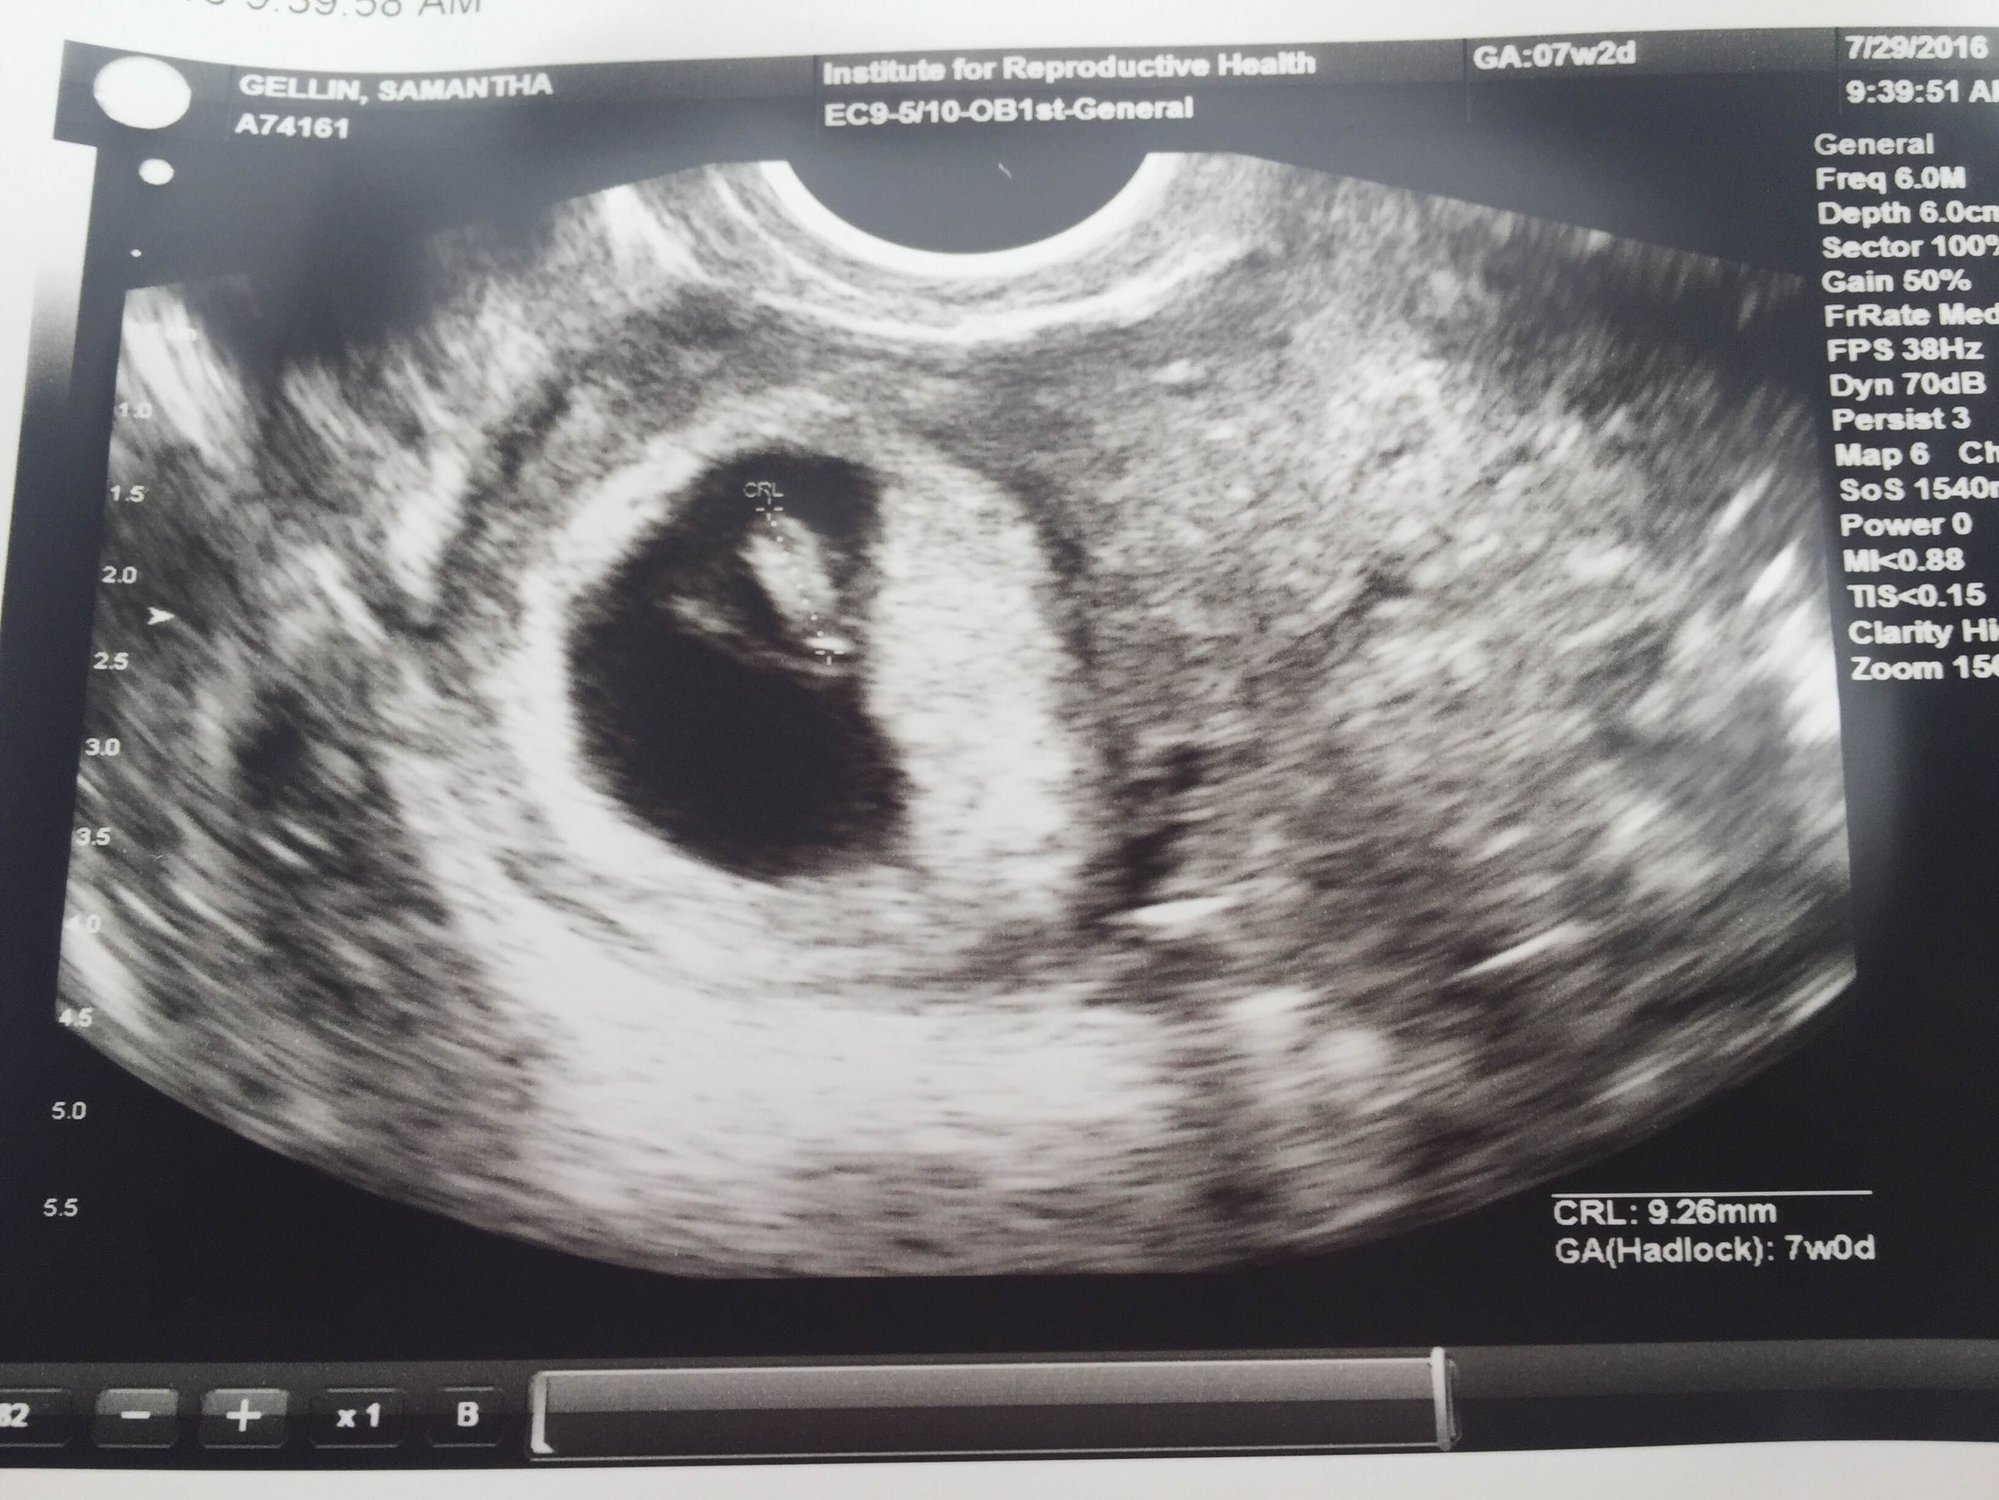

I got to see my two little ones and hear their heartbeats again this week at 7w4d. They are pretty clearly di/di. I "graduated" from the REs office and cried in the elevator leaving, it was really overwhelming. Sorry to keep posting all my ultrasound photos but staring at them is the only thing that keeps me from losing my mind with all the nausea and vomiting. And we haven't told anyone else so I have to keep telling you all!